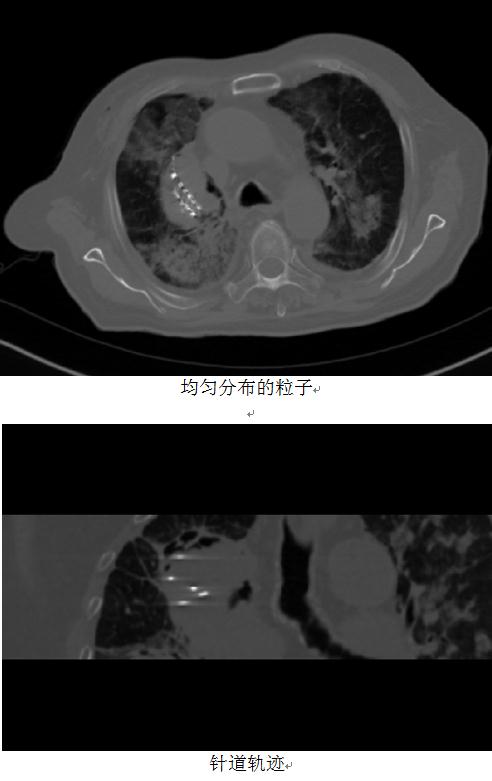

放射科宓主任医疗团队使用卓业科技的3D治疗系统(ZOYE-3DMS V1.0)设计出符合患者病情的个体化穿刺方案,并在3D打印联合模板的精准定位引导下,通过穿刺针道的均匀分布和放射剂量合理选择,为患者实施的手术达到了非常理想的治疗效果。

在3D打印联合模板辅助下的粒子治疗手术,在20分钟内就完成了整个手术过程,并达到了预期的治疗效果。这减少的是手术时间,是病人更少的伤痛,增加的是更理想的疗效,和更有把握的责任感。高新技术在更加开放纳新的团队中必将带来更高的效率和可能!